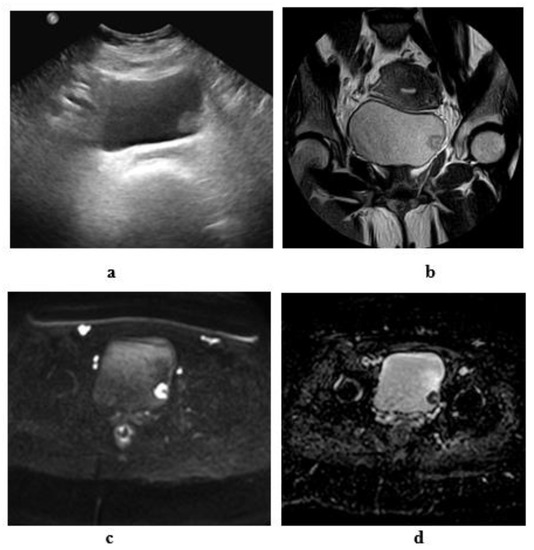

2.3. Ultrasonography

2.3.1. Conventional Ultrasonography

2.3.2. Color Flow Doppler Ultrasonography

2.3.3. Contrast-Enhanced Sonography

2.3.4. Three-Dimensional US

2.6. Magnetic Resonance Imaging

2.6.1. High-Resolution T2-Weighted Imaging (T2WI)

2.6.2. Diffusion-Weighted Imaging (DWI)

2.6.3. Dynamic Contrast-Enhanced (DCE) Imaging